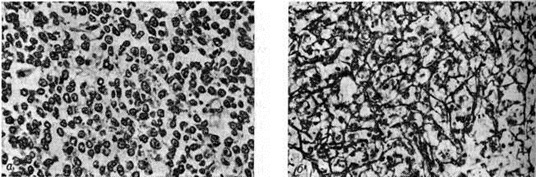

Ретикулосаркома кости первичнаяРетикулосаркома кости первичная (латынь reticulum сетка саркома; синонимы: моноцитома кости, ретикулоклеточная саркома кости) — солитарное злокачественное новообразование кости ретикулярно-клеточного происхождения. Локализуется обычно в длинных трубчатых костях, реже возникает в плоских костях или других отделах скелета. Впервые выделена как нозологическая форма в 1939 год Паркером и Джексоном (F. Parker, Н. Jackson). Ретикулосаркома кости первичная составляет около 3% всех первичных опухолей скелета. Чаще заболевают лица мужского пола в возрасте 15—30 лет. Этиология неизвестна. Описаны случаи возникновения Ретикулосаркома кости первичная на основе болезни Педжета (смотри полный свод знаний: Педжета болезнь). Первоначально опухоль всегда расположена внутрикостно с последующим частичным или полным разрушением компактного вещества. Опухоль представлена очагом мягкой серо-розовой ткани, не имеющим чётких границ. Сравнительно часто при Ретикулосаркома кости первичная в зоне очага поражения наблюдается патологический перелом с признаками вторичного репаративно-реактивного остеогенеза. Микроскопически основным структурным элементом являются опухолевые клетки лимфоидно-ретикулярного типа с более или менее выраженными признаками полиморфизма и атипии с овальными, бобовидными или подковообразными ядрами и достаточно чётко контурированной цитоплазмой (рисунок 1, а), Клетки Ретикулосаркома кости первичная по размерам несколько крупнее клеток саркомы Юинга (смотри полный свод знаний: Юинга опухоль). Иногда клетки содержат два или три ядра, обычно с хроматином в виде грубых неправильной формы глыбок. Часто наблюдаются фигуры митоза. В отличие от опухоли Юинга в Ретикулосаркома кости первичная почти постоянно удаётся выявить богатую сеть аргентофильных волокон, которые иногда оплетают почти каждую клетку (рисунок 1, б), В цитоплазме клеток Ретикулосаркома кости первичная не содержится гликоген. В периферических отделах опухоли часто наблюдаются признаки коллагенообразования иногда вплоть до формирования небольших фиброзных полей. В этих же участках опухоли можно видеть и очаги реактивного остеогенеза. Клинически заболевание отличается постепенным началом. Первыми симптомами являются боли в зоне очага поражения с иррадиацией вдоль нервных стволов по типу неврита или корешковых болей. Вначале боли интермиттирующие, иногда возникают только при физической нагрузке и лишь через несколько месяцев приобретают постоянный характер. В некоторых случаях боли локализуются в ближайшем к очагу поражения суставе. Часть больных (около 30—40%) обращается за медпомощью уже при наличии патологический перелома. Поэтому воспалительные и реактивные изменения нередко затрудняют диагностику. Ретикулосаркома кости первичная в 20—25% случаев метастазируют в костную систему, чаще всего в плоские кости черепа, лопатку, кости таза и ребра. Диагноз устанавливают с помощью комплексного клинического, рентгенологическое, радиоизотопного и морфологический исследования. Рентгенологические картина многообразна и зависит от фазы роста и локализации опухоли. Вначале появляется участок деструкции мелкозернистой, пористой, пятнистой структуры, который расположен в губчатом веществе (рисунок 2, а). В дальнейшем нарастает литический процесс, формируются очаги деструкции округлой или овальной формы с нечёткими очертаниями. Часто наблюдается несоответствие между мало выраженной клинические, симптоматикой и значительными рентгенологическое изменениями. Это обусловлено инфильтративным ростом опухоли, образованием внекостного её компонента, который не содержит известковых включений. Может выявляться пластинчатая деструкция компактного вещества (рисунок 2, б). Деструктивный процесс иногда характеризуется наличием крупных опухолевых узлов с плотными краями и различной степени «вздутием» кости, напоминающим костную кисту, а при наличии большого количества перекладин — остеобластокластому (рисунок 2, в, г). |